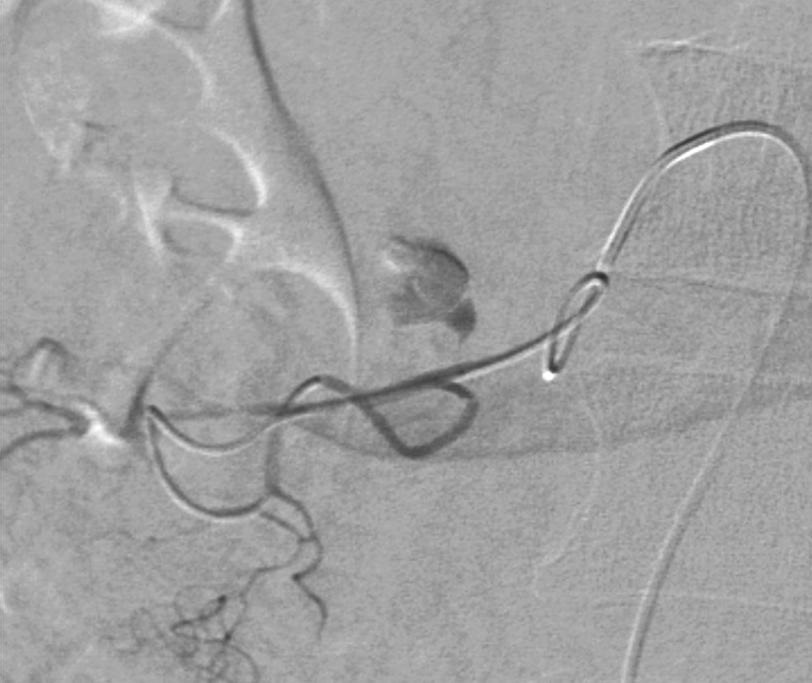

早期血管造影有关键作用【7~9】。血管造影发现动脉瘤和血管损伤为93%~96%,血管造影需要选择性注射直至静脉期,造影后的治疗计划取决于动脉瘤的类型和精确的血管解剖评价,动脉瘤的供血动脉等。 如果血管造影为阴性,主要由于间歇性出血(intermittent bleeding),静脉出血和弥漫性大面积毛细血管出血。有时需要经验性盲目栓塞或外科手术。栓塞的临床成功率为65%。 栓塞的目标是明确血管段阻塞(Definitive Segmental Vascular Exclusion),隔离动脉瘤腔的动脉供血【1,2,9】。 选择动脉瘤的近端和远端动脉闭塞,导丝导管通过动脉瘤腔时,需谨慎小心,避免动脉瘤破裂。必要时填塞动脉瘤防止复发和破裂,特别是多支动脉参与瘤腔供血时。 可用微弹簧栓子桥接方式(bridging method)栓塞动脉瘤。血管胶的应用仅在远端弹簧栓子放置失败或存在严重的凝血功能障碍时和弹簧栓子栓塞后再通。 病例一

病例二:慢性胰腺炎,急性腹痛和休克。动脉瘤弹簧栓子远近端栓塞

病例三,急性腹痛两周